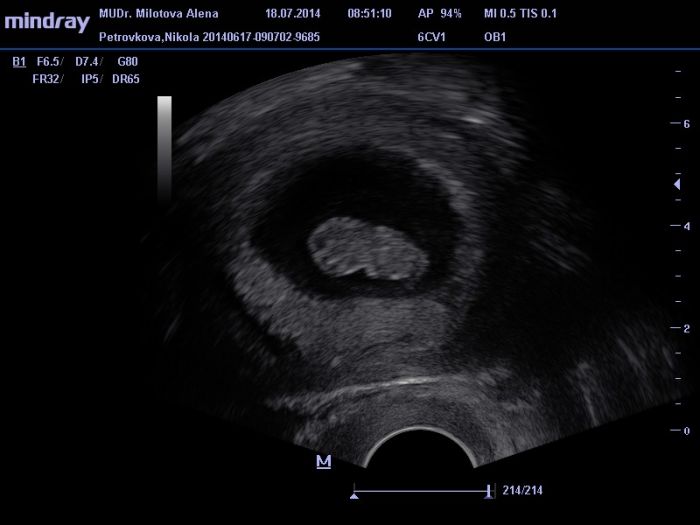

Ahojky holky tak mam po ko a vse v poradku akorad mi broucka nezmerila :( sakra ... Dalsi ko a rovnou zapis a odbery a moc 28.7. :) Mam radost ze pindik malej roste pupiiik :-* posilam i par fotecek :)

tak ted nevim jestli ty fotky vy uvidite :) takze jeste jednou :)